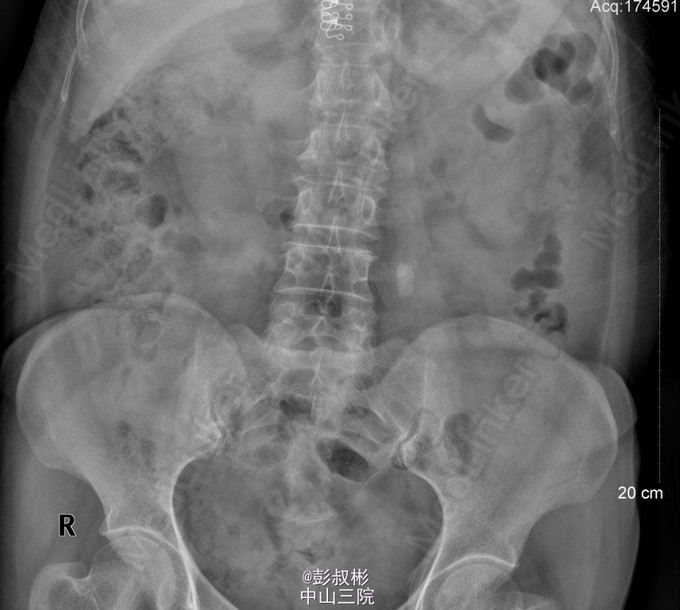

女性,56岁,左腰酸胀不适2年余。KUB:左输尿管上段结石,大小约16mm×10mm。腹部CT:左输尿管上段结石,并左肾、输尿管重度梗阻性积水。核素双肾动静态显像:左肾功能中重度减退,右肾功能正常。